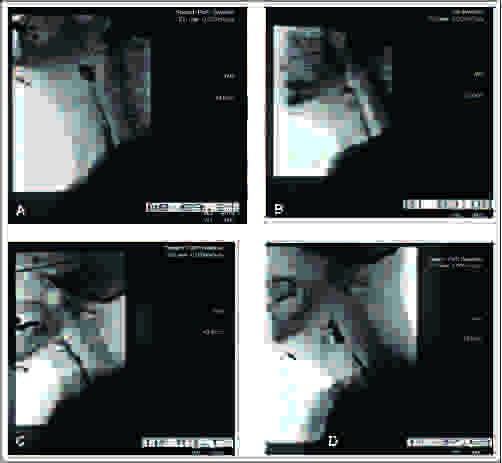

figure-1-pharyngeal-constriction-impairments